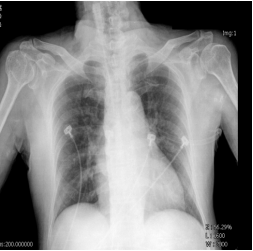

3. 82歲老婦人到院主訴五天來有日趨嚴重的呼吸困難。病史顯示30年前就有醫師告知心臟雜音,因無症狀,未曾有任何治療。近五年來運動耐受逐漸不佳,且偶有突發性悸動及心絞痛,特別在步行樓梯間更加惡化。住院當日清晨3點突然重度呼吸困難,因而急診住院。理學檢查:血壓110/62 mmHg;心跳90/分;頸靜脈怒張。心臟大小正常,但在右上胸骨緣及心尖部有Gr III/VI systolic murmur, S2減輕:其他所見尚無異常。其胸部X光、心臟超音波及心電圖如圖。WBC,5.2 k/micro L;AST,21U/L;CK,111U/L;CK-MB,14.6U/L;Troponin I,0.06 ng/ml。請問下列何項處置最恰當? (A) Percutaneous coronary intervention (B) Aortic valve replacement (C) Nitroglycerin IV infusion at the rate of 15mcg/min (D) Titrate PO carvedilol starting from 3.125 mg and reassess in 3 months (E) Treating with IV digoxin 0.125mg in conjunction with IV bolus Furosemide 20mg and then 20 mg BID

胸部 X 光